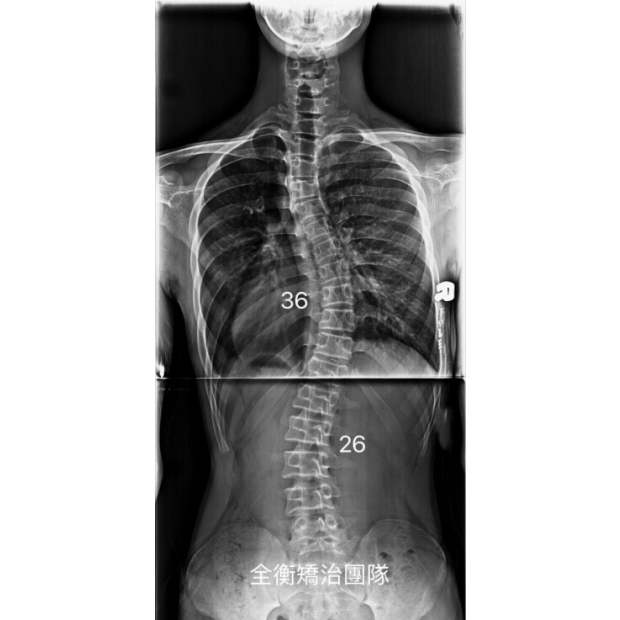

16歲脊椎側彎男孩 胸彎36度 腰彎26度 -